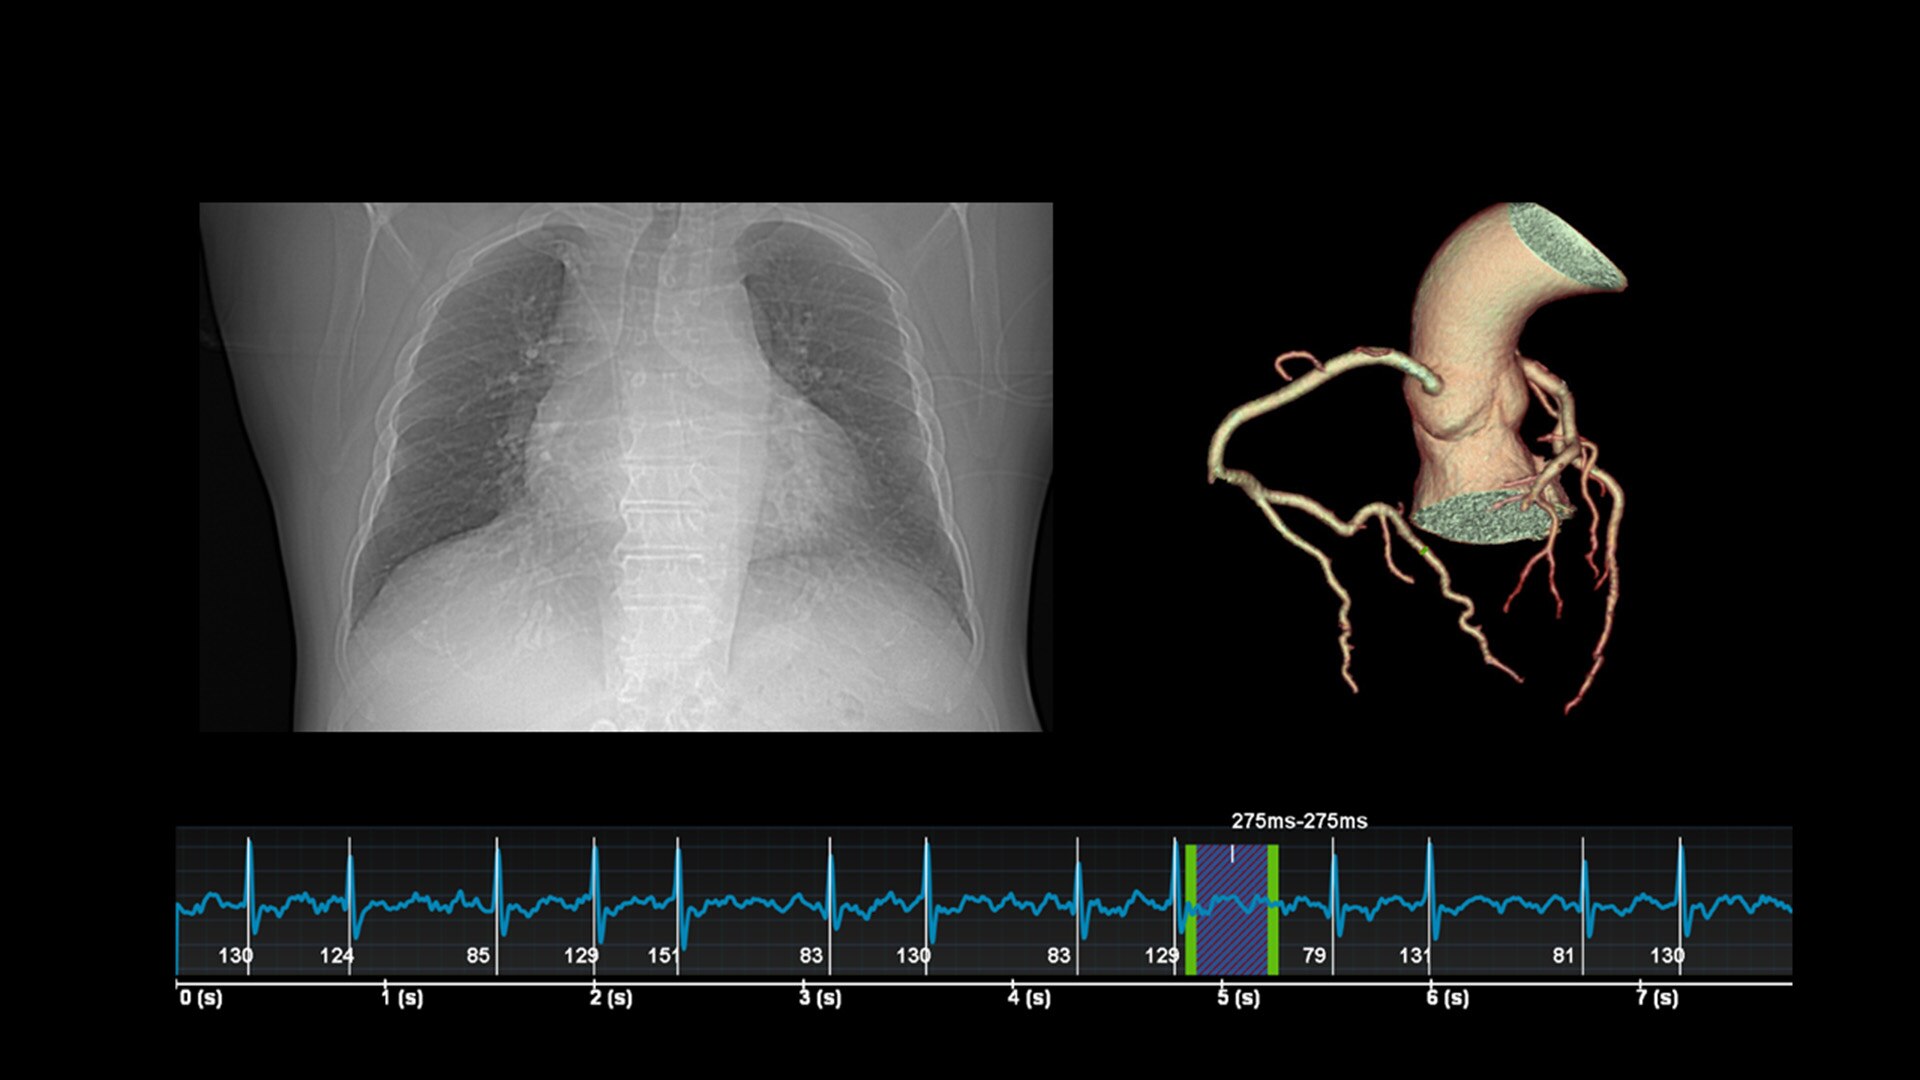

Unlimited 1-Beat Cardiac is designed to provide consistent, high-quality imaging for accurate diagnoses, even in challenging patients with atrial fibrillation, breath-holding difficulties, heavily calcified coronaries, in-stent restenosis, and situations where an ECG trace is unavailable.

Revolution Vibe's AI-powered workflow streamlines the entire cardiac CT process, from pre-scan to post-scan. It delivers accurate, automatically personalized scans for each patient, reducing dependency on user experience and enabling your team to achieve confident results swiftly.